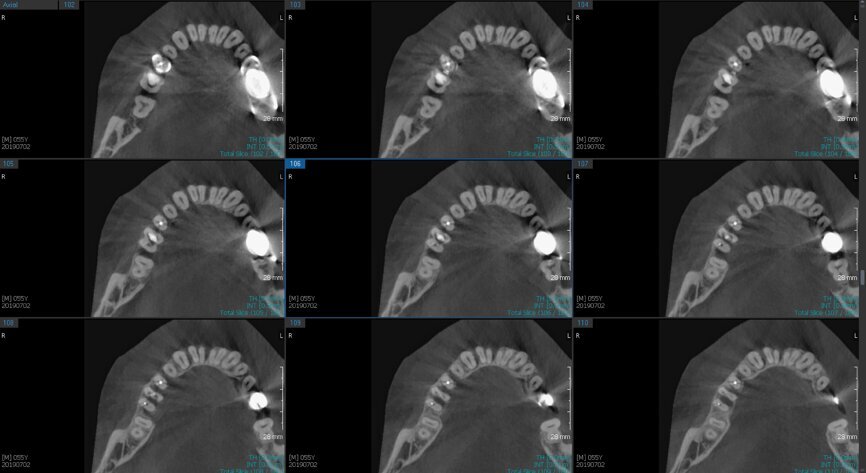

Fig.2a: Pre-op CBCT images of tooth #46: No obturation material in the distal and mesiobuccal canal (a); scanty obturation of the canals and breach of the floor of the pulp chamber, no obturation beyond a few millimetres down the orifice (b & c); radiolucency in the furcation area and periapical region of both roots (d -g).

Fig.2b: Pre-op CBCT images of tooth #46: No obturation material in the distal and mesiobuccal canal (a); scanty obturation of the canals and breach of the floor of the pulp chamber, no obturation beyond a few millimetres down the orifice (b & c); radiolucency in the furcation area and periapical region of both roots (d -g).

Fig.2c: Pre-op CBCT images of tooth #46: No obturation material in the distal and mesiobuccal canal (a); scanty obturation of the canals and breach of the floor of the pulp chamber, no obturation beyond a few millimetres down the orifice (b & c); radiolucency in the furcation area and periapical region of both roots (d -g).

Fig.2d: Pre-op CBCT images of tooth #46: No obturation material in the distal and mesiobuccal canal (a); scanty obturation of the canals and breach of the floor of the pulp chamber, no obturation beyond a few millimetres down the orifice (b & c); radiolucency in the furcation area and periapical region of both roots (d -g).

Fig.2e: Pre-op CBCT images of tooth #46: No obturation material in the distal and mesiobuccal canal (a); scanty obturation of the canals and breach of the floor of the pulp chamber, no obturation beyond a few millimetres down the orifice (b & c); radiolucency in the furcation area and periapical region of both roots (d -g).

Fig.2f: Pre-op CBCT images of tooth #46: No obturation material in the distal and mesiobuccal canal (a); scanty obturation of the canals and breach of the floor of the pulp chamber, no obturation beyond a few millimetres down the orifice (b & c); radiolucency in the furcation area and periapical region of both roots (d -g).

Fig.2g: Pre-op CBCT images of tooth #46: No obturation material in the distal and mesiobuccal canal (a); scanty obturation of the canals and breach of the floor of the pulp chamber, no obturation beyond a few millimetres down the orifice (b & c); radiolucency in the furcation area and periapical region of both roots (d -g).

When I had a close look at the preoperative radiograph from the referring dentist (Fig. 1a), I observed that there was insufficient obturation of the mesial canals and almost no obturation of the distal canal. Both roots displayed periapical radiolucency. The clinical examination revealed a Grade I mobility, and the tooth was tender to percussion. The periodontal examination ruled out any pockets and loss of attachment. We took an intra-oral periapical radiograph (Fig. 1b), from which we observed the loss of coronal structure and a large radiolucent area over the furcation area and the periapical area of both the mesial and the distal roots. A CBCT scan of tooth #46 was advised to check for any details that may have been missed in the intra-oral periapical radiograph (Figs. 2a–g). From the CBCT scan, it could be observed that there was inadequate obturation of the distal canal on the horizontal plane, no obturation beyond the middle third in the mesial canals and a breach of the floor of the pulp chamber. The questionable prognosis was explainedto the patient, and written consent was obtained.